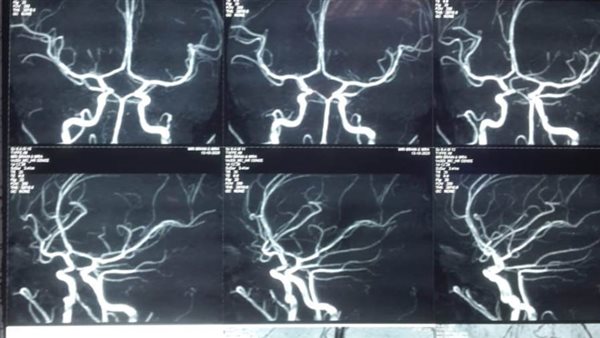

وكان المستشفى استقبل طفلة تبلغ من العمر 11 عاما، تعاني من نزيف ببطينات المخ أدى إلى تدهور شديد فى درجة الوعي لارتفاع ضغط السائل النخاعي على جذع المخ، وتم التدخل الجراحي العاجل من الفريق الطبي، وعمل الجراحة بطريقة بسيطة باستخدام جهاز ( CVP)، وتحويل مسار السائل تحت فروة الرأس ventricluosubgaleal shunting.